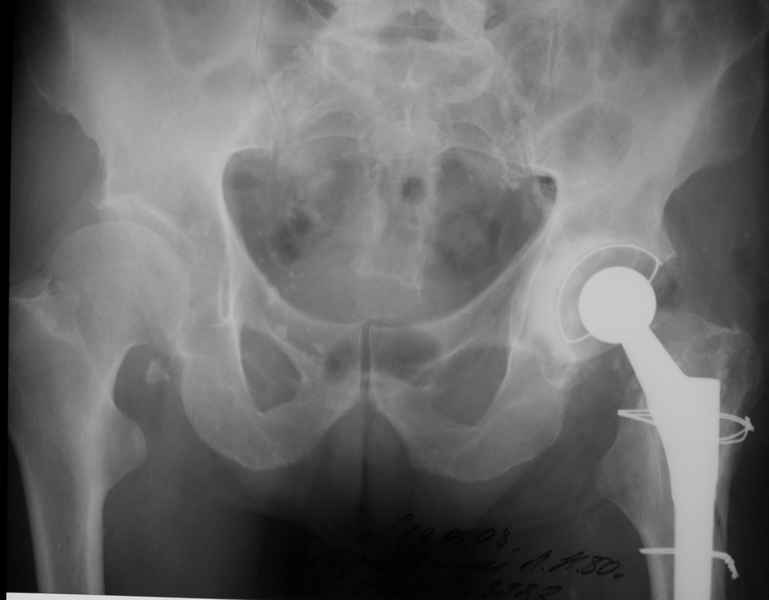

Уважаемые коллеги, продолжая дискуссию, начатую на "Вреденовских чтениях", хочу сказать, что принципиально сущестует два возможных варианта лечения.

1.Остеосинтез на ножке. Мне кажется, что применительно к этому случаю малоперспективный вариант. Синтез хорош, когда можно его выполнить в малоинвазивном исполнении и достигнуть стабильности. Действительно, если ножка б/цементной фиксации после этого не будет иметь фиксации, то ревизия не будет иметь проблем. В представленном случае стабильность синтеза сомнительная, а проведение доп.иммобилизации приведет к контрактуре суставов.

2. Применение ножки дистальной фиксации, мы отдаем предпочтение ножке Вагнера с фиксацией проксимального отдела на ножке. Более травматичное вмешательство, но при стабильной фиксации ножки реабилитация идет в обычном режиме.

Хочется показать два подобных случая, П-ка З. 72 лет и п-т Г. 80 лет. Сразу принимаю замечание, что это были ножки цементной фиксации, просто под руками не было бесцементника.

Пациента удалось осмотреть недавно. Достигнутый результат сохраняется. Перелом бедра сросся. Конечность опорная и безболезненная, ходит без трости. Ножка, похоже, реинтегрировалась, как и надеялись. Снимки и фото в приложении. Комментарии приветствуются.

Надо ли что-то делать дальше, как полагаете? Убрать винты? Убрать "удлинитель ножки"? Или оставить все, как есть? Спасибо заранее.